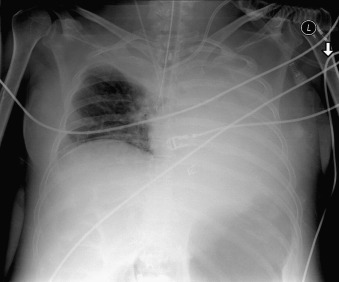

Complications of intubation ( Figs. 25-1 to 25-10 ) and ventilation that are apparent on a chest radiograph are often potentially life-threatening and should be excluded on every radiograph, both immediately following intubation and with each subsequent radiograph. These possibilities are listed in the following sections.

Bronchus Intermedius Intubation

(This involves deep intubation of the right mainstem bronchus with the tip beyond the take-off of the upper lobe bronchi.)

Possible volume loss of the right upper lobe

Possible overinflation of the right lower and middle lobes

Possible volume loss of the left lung